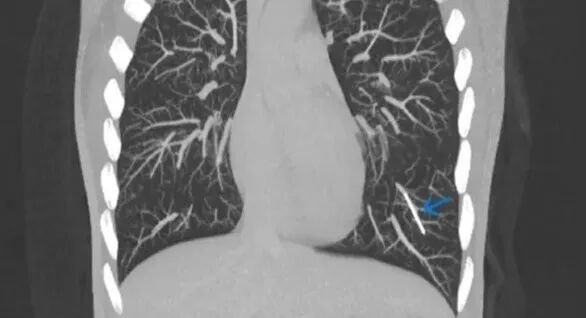

流浪植入物

通过CT检查,医生在一位英国女性的肺里发现了意想不到的东西:一根失踪多年的避孕植入物[8]。

用于避孕的皮下埋植物通常很安全,但在罕见的情况下,它也有可能在人体内游走,甚至到达肺部。图中蓝色箭头标记的小棒就是进入肺部动脉的“流浪植入物”。 | Kareem et al.

这种植入物是火柴大小的弹性棒状物,它原本应该埋植在使用者手臂的皮下,通过缓慢释放孕激素发挥避孕功能。皮下埋植是效果最可靠的避孕手段之一,但在罕见的情况下,植入物有可能会在体内移位。

在这位女患者体内,植入物卡在了左下肺的一段动脉里。它应该是首先进入了手臂的静脉,然后顺着血液回流来到心脏,最后到达了肺部。医生推测,这种情况可能与植入时操作不当有关。